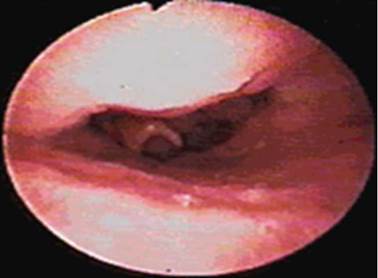

El protocolo comienza con una revisión fibroscópica estática con descripción de la morfología de cada paciente, la cual se inicia a nivel nasal, haciendo énfasis en el tamaño, forma e inserción de los cornetes, la anatomía septal y sus relaciones (Figura 1). Un sitio importante en la fisiología respiratoria es el área de la válvula nasal, el cual debe ser un sitio que el examinador evalúe de forma rutinaria para descartar vibración, colapso o estrechez a este nivel, pues su estrechez ocasiona problemas obstructivos considerables. Luego, se continúa con la evaluación del espacio nasofaríngeo, evidenciando la presencia de remanentes adenoideos o masas que pueden ser hallazgos frecuentes en pacientes con apnea obstructiva 8. Por último, se realiza una vista estática palatofaríngea superior -cuya presentación más usual es ovalada- y los hallazgos de cambios de esta morfología hacen suponer alteraciones en las estructuras anatómicas ubicadas a este nivel.

Vista endoscopia nasal de una septodesviación.

Figura 1: Vista endoscopia nasal de una septodesviación.

Fuente: Documento obtenido durante la realización del estudio.